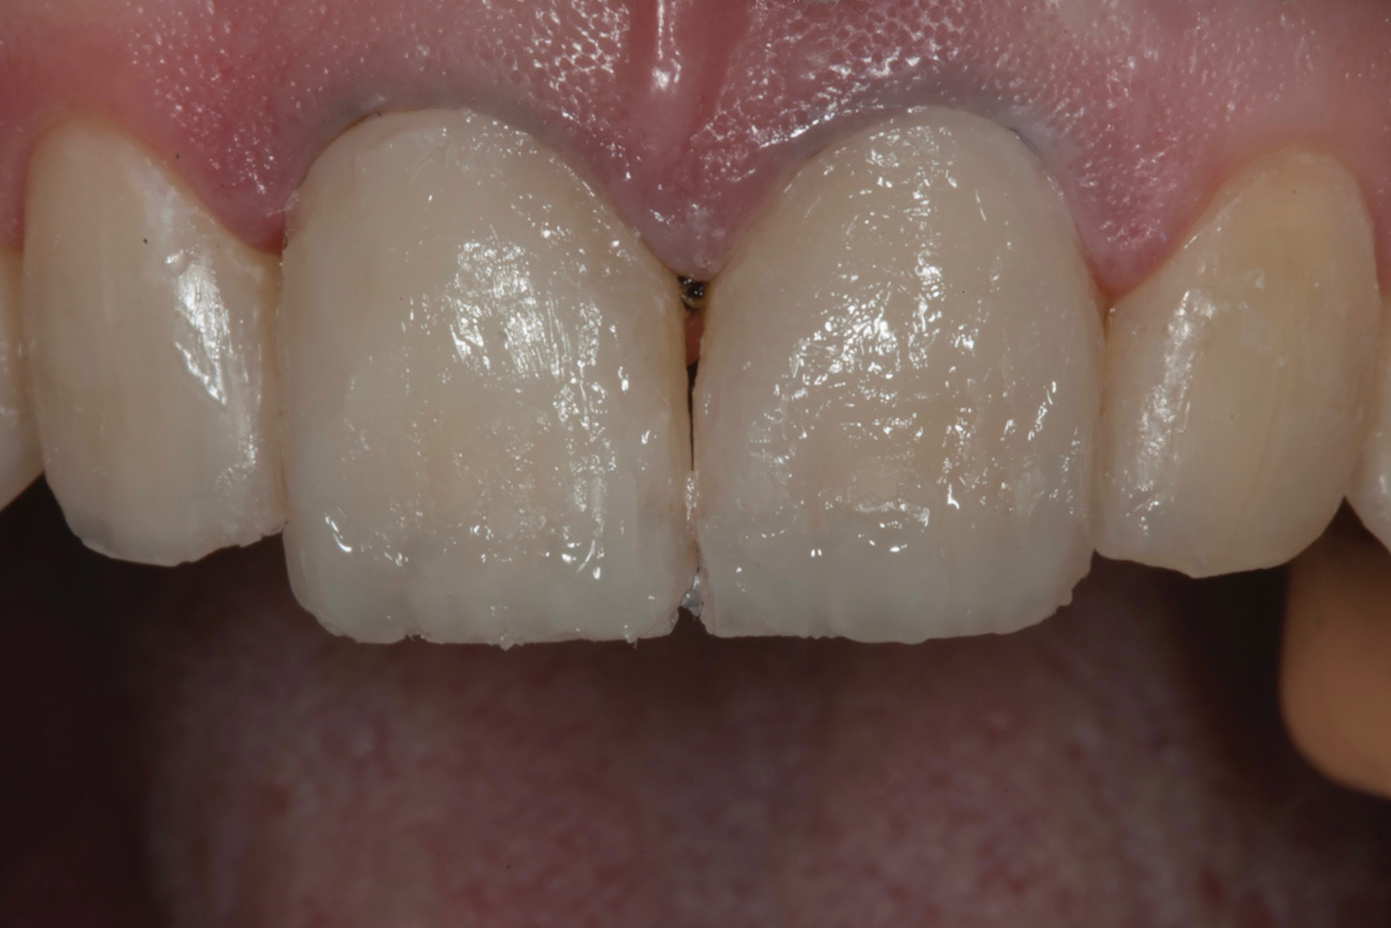

Fig 12. Postoperative upper anterior view and occlusal views of the upper and lower arches.

Figure 12

Fig 13. Postoperative upper anterior view and occlusal views of the upper and lower arches.

Figure 13

Fig 14. Digital smile design software enables parameters of interim prosthesis to be facially generated; (Fig 12) front view, (Fig 13) occlusal view, (Fig 14) 12 o’clock view.

Following caries treatment and tooth preparation (Figure 6), teeth Nos. 4 through 13 were restored with direct composite veneers in stages (Figure 7 through Figure 9). Using a hybrid composite for the lingual shelf and dentin layer provides wear resistance and strength for the restoration.14,15 (The lowest wear rates for restorations and the opposing dentition occur with metal alloys, machined ceramics, and microfilled hybrid resin composites. Any adjusted and unpolished porcelain surface would elicit the most wear on the opposing teeth.11)After the composite veneers were finalized, a monolithic lithium disilicate crown was placed on tooth No. 12 during a subsequent appointment, and occlusal equilibration was carried out. Final photographs were taken a couple of weeks later (Figure 10 through Figure 14).